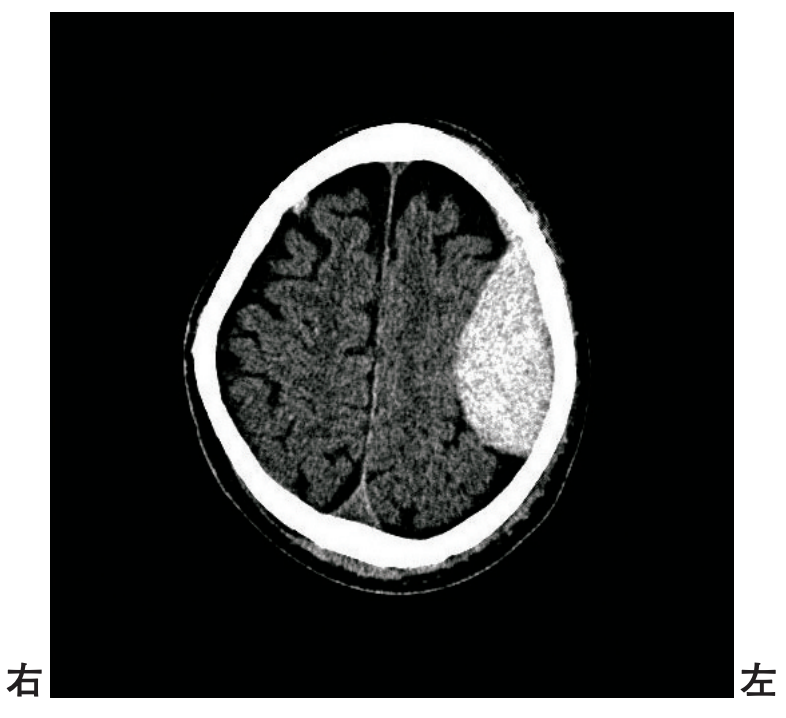

頭部CTを別に示す。

所見として考えられるのはどれか。

• くも膜下出血

• 硬膜外血腫

• 硬膜下血腫

• 脳動静脈奇形

• 皮質下出血